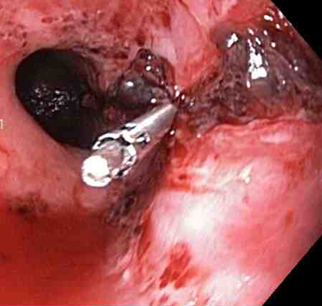

[Figure caption and citation for the preceding image starts]: Mallory-Weiss tear after adrenaline injection (the bleeding has stopped, allowing better visualisation of the lesion)From the collection of Juan Carlos Munoz, MD, University of Florida [Citation ends].

[Figure caption and citation for the preceding image starts]: Adrenaline is injected locally around the site of the Mallory-Weiss tearFrom the collection of Juan Carlos Munoz, MD, University of Florida [Citation ends].